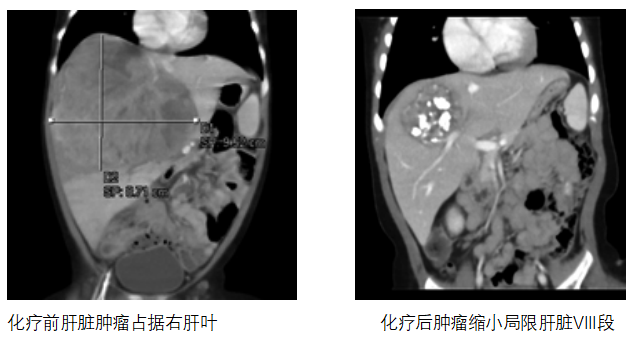

患儿当时不到7个月,而肝脏肿瘤几乎占据整个右半肝脏,为提高患儿生存率及生活质量,李索林教授团队为其制定术前新辅助化疗,化疗后影响评估能否肝切除术。经过4个疗程规范性化疗后,再次进行影像学检查显示患儿肝脏肿瘤明显缩小,且肿瘤局限在肝脏VIII段位置。

手术切除病灶是治愈肝母细胞瘤的根本途径,现在精准肝切除已替代传统肝切除术,走向肝母细胞瘤综合治疗体系的核心。但处于肝VIII段的肿瘤位置暴露困难、毗邻结构复杂、手术难度大、风险高等原因,一直被医学界看作是腹腔镜肝切除的禁区。